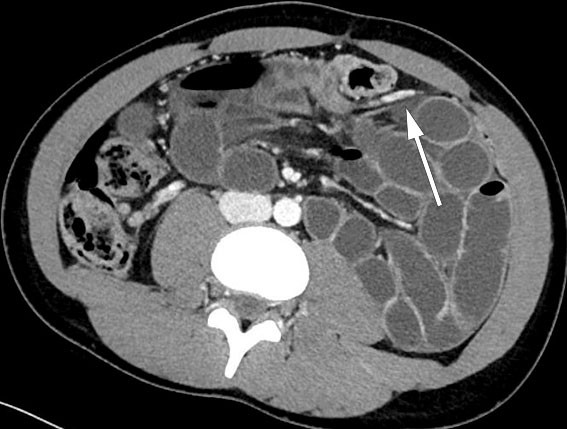

The CT scan revealed a dilated small bowel with sudden calibre change in the central and left region of the abdomen, localised misty mesentery towards the dilated small bowel and faecalised small bowel content. Bowel ischaemia was not suspected, and no intra-abdominal free air or fluid was seen. The overall radiological evaluation raised suspicion of adhesive small bowel obstruction, which was not entirely consistent with the patient's age and absence of previous abdominal surgery.

Laparoscopy was performed under general anaesthesia and found a small amount of intra-abdominal free fluid. Large areas of the small bowel were dilated. We started to reposition the small bowel to the right, firstly from proximal to distal and then in a proximal direction from the ileocaecal junction. It appeared that the small bowel was herniated under a 'cord' attached to the descending colon. On closer inspection, vascular structures could be made out, and we could not rule out the mesentery being narrow with a defect (Figure 1). Due to a large amount of dilated bowel in the surgical field, limited space and uncertainty about whether all the bowel had been repositioned, it was decided to convert to laparotomy. With a midline approach, we found mechanical small bowel obstruction from a left paraduodenal hernia with large areas of the small bowel herniated to the left, posterior to the inferior mesenteric vein. The repositioned small bowel appeared viable since there was good bowel motility and good blood circulation. Continuous sutures were placed with patent closure of the opening in the mesentery, without injuring the vascular structures.

On review of the patient's CT images, it could be seen that the inferior mesenteric vein runs anterior to the herniated small bowel loops. This was also seen intraoperatively and was consistent with the diagnosis of paraduodenal hernia (Figure 2).